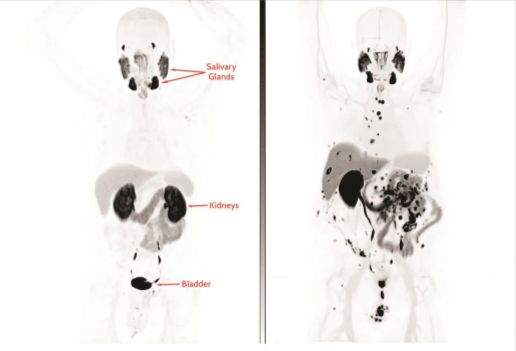

Imaging Scans are Used to Evaluate for Metastasis

Left panel: A patient’s PSMA PET scan shows no metastases.

Right panel: A patient’s PSMA PET scan shows extensive metastases to the bones, lymph nodes, and lining of the abdomen (peritoneum). Note that uptake to the salivary glands is normal, since PSMA is expressed there. Also note that the contrast is emptied through the kidneys and bladder, and this is also normal.